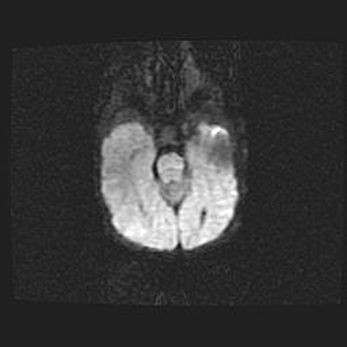

Лейкомаляция с кистозно-глиозной дегенерацией головного мозга.

Возраст: 2 месяца 25 дней

Вес: 6400 г

Окружность головы: 40 см

Срок гестации: 41 неделя

Лейкомаляцию относят к ишемически-гипоксическим повреждениям головного мозга, диагностируемым у новорожденных. При лейкомаляции в головном мозге обнаруживают очаги некроза, возникшие после тяжелой гипоксии и нарушения кровотока. В процессе морфогенеза очаги проходят три стадии: 1) развития некроза, 2) резорбции и 3) формирования глиозного рубца или кисты. Перивентрикулярная лейкомаляция (ПЛ) встречается примерно в 12% случаев среди новорожденных, обычно – у недоношенных детей, причем, частота ее зависит от массы, с которой младенец появился на свет. Наибольшее число малышей страдает лейкомаляцией, если масса при рождении 1500-2500 г.